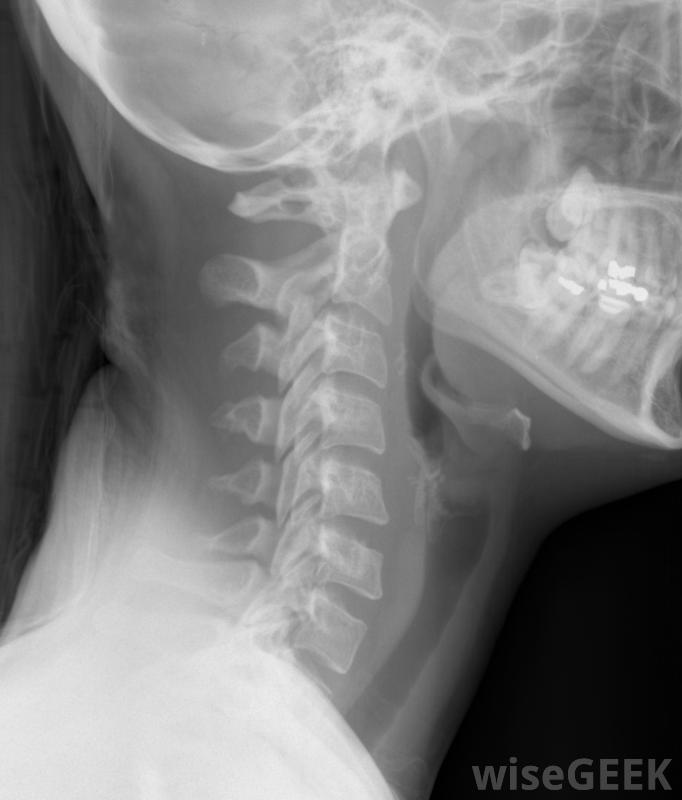

頸神經根病是指頸部神經受到刺激或神經根離開脊柱時受到壓迫-通常稱為神經卡壓。這種情況的主要原因是退行性改變、椎間盤突出和脊柱不穩。通常,頸神經根病的第一個癥狀是頸部疼痛或肌肉僵硬。手臂、肩膀、背部和胸部也可能疼痛,手、手臂和肩部也會虛弱或麻木。包括頸椎在內的頸部X光片。導致頸神經根病的原因很多。隨著年齡的增長,它們的骨骼和軟組織發生退行性改變。脊柱椎間盤失去水分并開始塌陷,從而導致椎骨之間的間隙變窄。小關節(位于相鄰椎骨之間和后面的關節)由于壓力增加而受到刺激而變大,因此壓迫神經引起疼痛。頸神經根病可能導致嚴重的頸部疼痛椎間盤突出也可引起頸神經根病,要么椎間盤被推離原位,要么椎間盤外壁的環形物受傷破裂,從而導致核內物質擠出椎間盤椎間盤突出可能是由于沉重的、反復的抬舉、扭曲或彎曲而使椎間盤核受到額外壓力的結果,也可能是由于椎間盤的自然變化造成的。椎間盤容易撕裂和破裂,并用疤痕組織修復,隨著時間的推移,疤痕組織會使椎間盤變弱頸椎神經根病可由椎間盤突出引起,脊柱不穩是頸神經根病發病的另一個原因包括脊椎骨間的額外運動,從而對頸部神經造成壓力。有時由于嚴重的頭部或頸部損傷導致支撐韌帶撕裂或拉伸而發展。此外,患有結締組織疏松的疾病的人也可能出現脊柱不穩信息技術;頸神經根病患者在從頸神經根病康復時,通常戴一到兩周的頸領。頸神經根病的癥狀是由于壓迫受刺激的神經引起的。頸部、手臂、肩部疼痛,背部和胸部很常見,頭痛也很常見。通常,神經會發生變化,比如肩部、手臂或手部的肌肉麻木、刺痛和無力。此外,上臂肌肉的反射也會受到影響如果不是頸椎病的治療方法,神經根病會迅速惡化用于緩解頸痛和背痛等癥狀取決于椎間盤和椎骨損傷的嚴重程度。醫生通常會鼓勵頸部固定,臥床休息幾天,并使用軟領子一到兩周與理療師一起工作是另一種治療方式。最初是為了緩解疼痛和炎癥。物理治療有多種選擇,如使用牽引力拉伸頸部關節和肌肉,或用電刺激來緩解疼痛。也可以開藥,如消炎藥、肌肉松弛劑或麻醉藥品,用于嚴重的頸神經根病患者。沉重而重復的舉舉舉可導致椎間盤突出,從而導致神經卡壓。